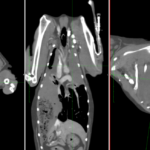

14歳のイタリアングレーハウンドが主訴として発咳を呈し、CT検査により左右両側の肺葉捻転が疑われた。肺葉捻転は稀であり、特に左右両側で発生することは極めて珍しい。左右肋間開胸術を実施して肺葉切除を行った。手術ではTA30Vステープラーを使用し、迅速かつ安全に肺葉切除が行われた。術後の経過は極めて良好であり、術後5日目には退院が可能となった。高齢犬でありながら、迅速な診断と適切な外科的介入が回復に寄与した。左右両側の肺葉捻転は非常に稀なケースであり、この症例は早期診断と外科的治療の重要性を示している。特にCTによる正確な診断と、適切な外科器具の使用が良好な術後経過につながった。肺葉捻転は自然発生的に、または乳び胸、外傷、腫瘍、慢性呼吸器疾患、あるいは過去の胸部外科手術などに伴って起こる。イヌの肺葉捻転は右中葉がもっとも多く(43%)、ついで左前葉に多く(35%)に起こることが報告されており、胸の深い犬種では右中葉に、小型犬種では左前葉に捻転が起こりやすいとされている。複数の肺葉に捻転が見られたことは稀である。